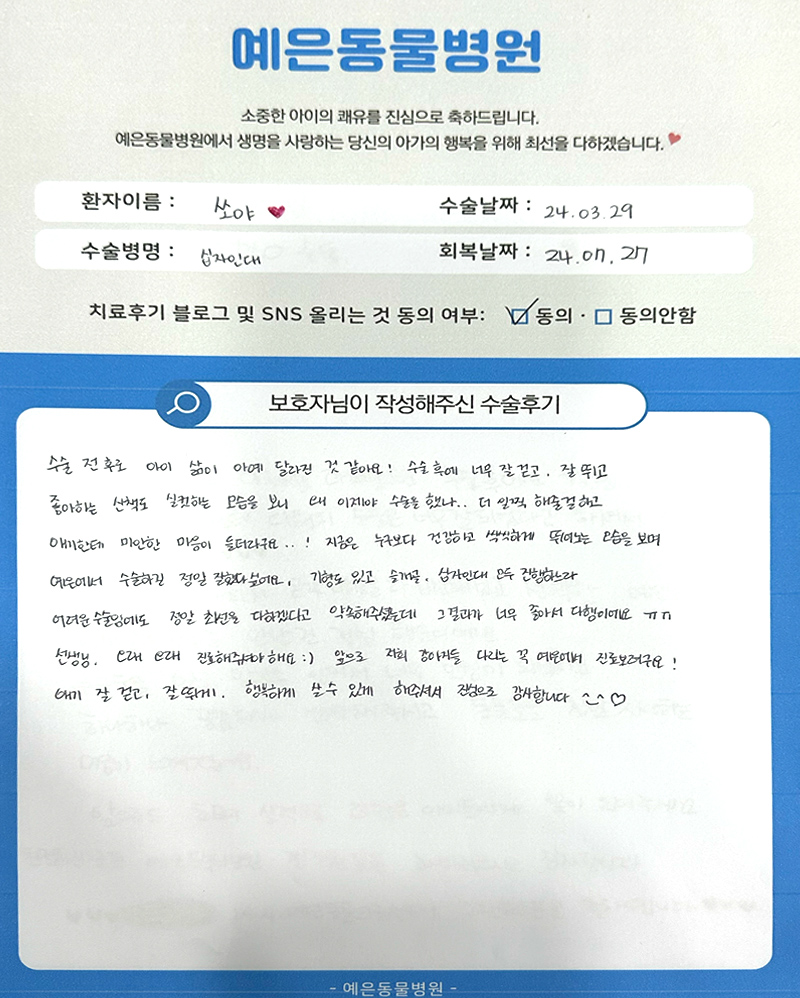

보호자님들이

직접 작성해주신

정형외과 수술 후기 모음

돋보기를 눌러 크게 확인해보세요.

보호자님들이

직접 작성해주신

정형외과 수술 후기 모음

돋보기를 눌러 크게 확인해보세요.